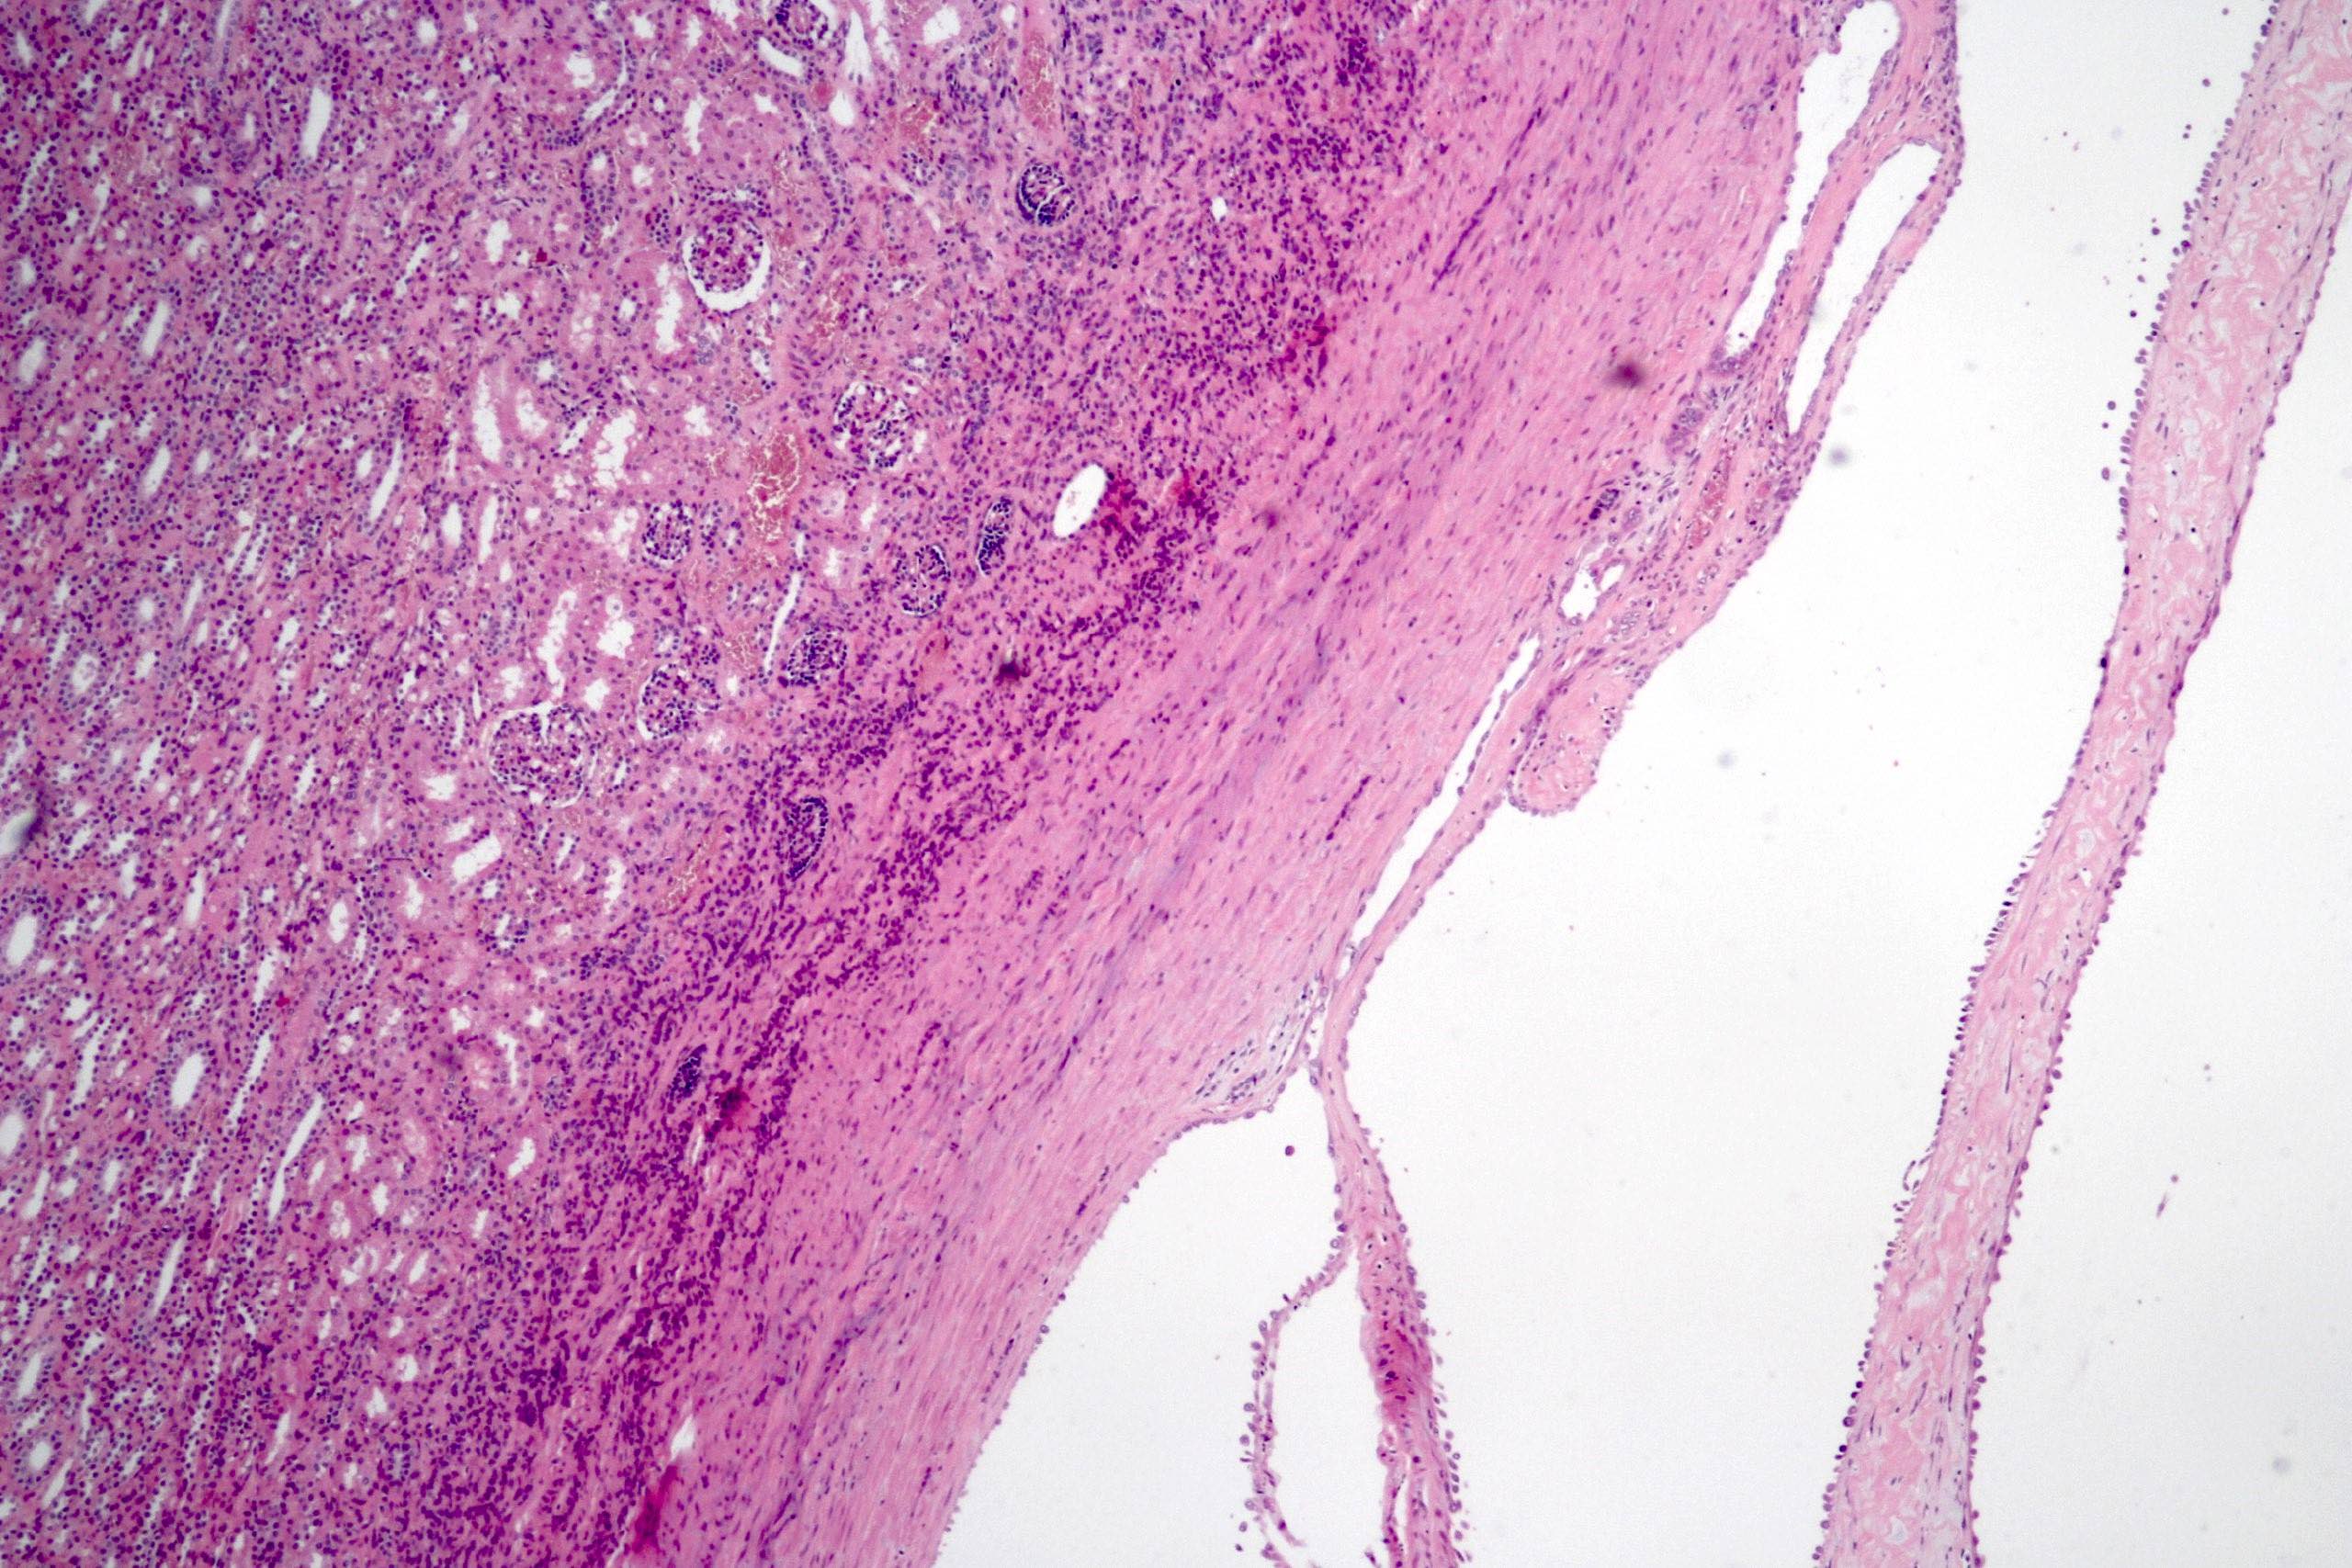

Microscopic (histologic) description

- Cysts lined with flat / cuboidal / hobnail cells (or are denuded)

- Epithelial elements consist mainly of mature and immature / abortive tubules and small papillae resembling immature glomeruli

- Key histological findings of the variably cellular septa include

- Nephroblastomatous epithelial elements

- Islands of undifferentiated blastema and differentiated mesenchymal elements (skeletal muscle and less often cartilage and fat) (J Urol 2010;183:1585)

- Focally, the septal elements may protrude into the cystic spaces in microscopic papillary folds

Microscopic (histologic) images

Contributed by Americo Brilhante, M.D. and Daniel Athanazio, M.D., Ph.D.